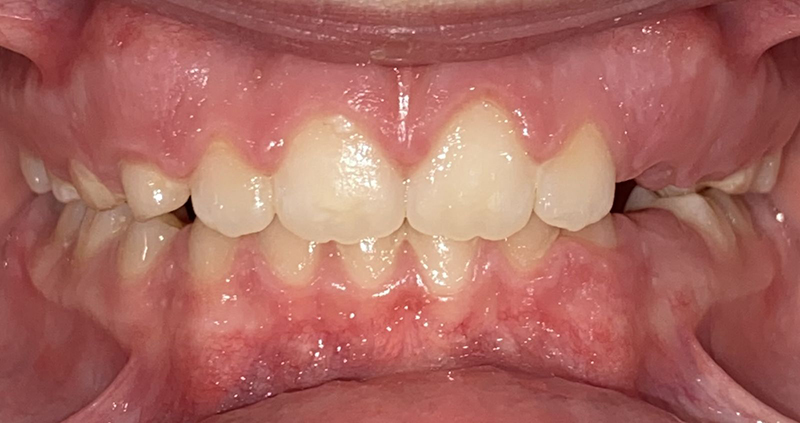

Actual Patient: Leanna

Img Before 2 2 Img After 2 1

Severe “Overbite”, BUCK TEETH, Narrow Jaws, Severe Deep Bite, Mouth breathing

Leanna Before 1 Leanna After 1 1

Treatment Time:

7.5 months

Front View

Top View

Right & Left Sides